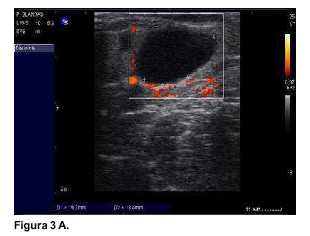

En todas las pacientes la neovascularización se objetivó precozmente mediante la ecografía. En las imágenes obtenidas (figuras 1A, 2A y 3A), se observan como zonas coloreadas en rojo y naranja. Desde el punto de vista endocrino la evolución se presenta en las gráficas contenidas en las figuras (figura 1B: caso 1, figura 2B: caso 2, y figura 3B: caso 3). Se destaca que todas las pacientes presentaban valores normales de E2 y FSH en el preoperatorio.

La tercera paciente (figura 3) presentó valores de castración (FSH: 100 mU/ml) que persistieron durante dos meses, al tercer mes aumentó el estradiol y bajó la FSH, allí aparecen los primeros folículos. Al cuarto mes se restablece la función normal acompañada de folículos de mayor tamaño y se restablecieron ciclos menstruales normales.

En estos tres casos fue posible sacar conclusiones de los autoinjertos de corteza ovárica a mediano plazo. A diferencia del caso publicado recientemente por nuestro grupo, en el que se mantuvo un ovario intraabdominal translocado(13), en estos casos la evolución depende exclusivamente de los injertos heterotópicos. La ecografía Power Doppler evidencia la enorme capacidad de neo-vascularización que tiene el tejido ovárico. Se trata de un evento precoz, que ya puede observarse dentro de la primera semana. Desde el punto de vista endocrinológico las pacientes, partiendo de una función normal, y luego de operadas, atraviesan un período de "castración" con una FSH muy elevada, 50 mU/ml (paciente 1), 100 mU/ml (paciente 2) y 110 mU/ml (paciente 3), con E2 muy bajo (menor de 10 pg/ml en todas). El primer signo de recuperación es un ascenso del E2 sanguíneo que ocurre al segundo mes en la paciente 1, al cuarto mes en la paciente 2, y al tercer mes en la paciente 3. Finalmente, se produce un descenso de la FSH a valores próximos a la normalidad. La reducción de la FSH está señalando la reestructuración de la granulosa folicular capaz de secretar inhibina, que realiza un "feed back" negativo a nivel hipofisiario con la FSH. En las tres se desarrollaron folículos en maduración, que coincidió con la normalización del estradiol.